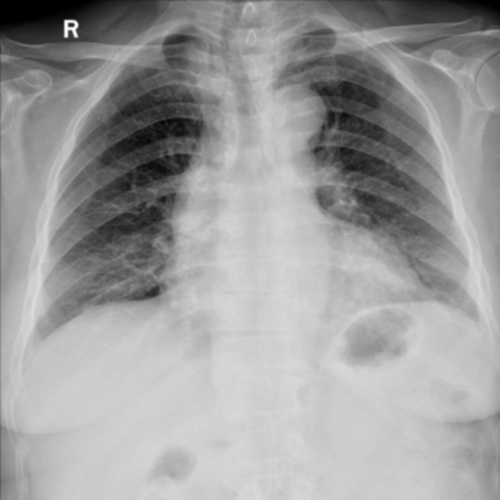

To pre-train a high-performance X-ray foundation model, the first thing we need to do is the collection of large-scale X-ray images. Therefore, a large-scale and high-resolution dataset that contains X-ray medical images is collected for the pre-training. Some representative samples are visualized in Fig. 3.